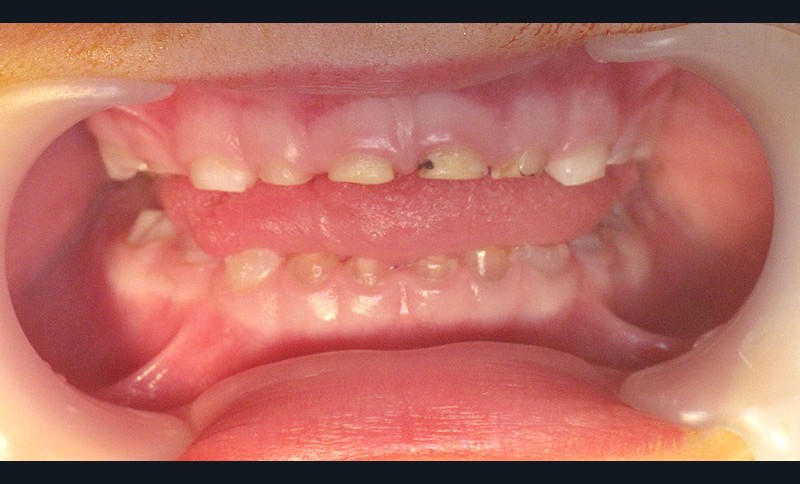

Teinte opalescente grise à jaune ambrée, couronnes globuleuses, calcifications intra-pulpaires, racines fines et courtes, attrition précoce, nécrose aseptique… Ces anomalies cliniques et radiographiques décrivent le tableau de la dentinogenèse imparfaite (DI) isolée de type 2. Cette anomalie génétique à transmission autosomique dominante est liée à un défaut de DSPP, gène de la sialophosphoprotéine dentinaire [1, 2]. Des anomalies dentinaires similaires résultent également de mutations de ce gène. Les avancées en recherche génétique tendent à réunir ces pathologies sous une même étiologie.

Un diagnostic précoce est primordial, car il existe aussi une forme associée à une anomalie osseuse, l’ostéogenèse imparfaite. Le chirurgien-dentiste est donc au premier plan pour dépister ces anomalies et limiter dès le plus jeune âge leurs conséquences infectieuses, fonctionnelles et esthétiques.